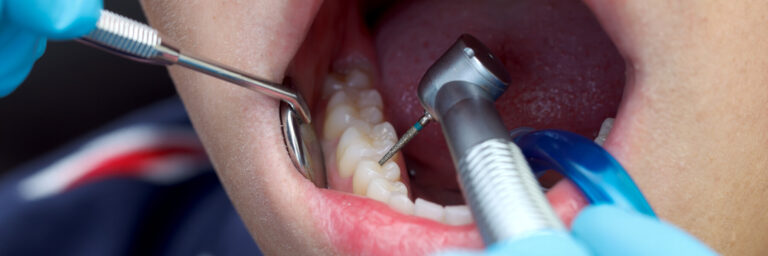

Unsere moderne Zahnarztpraxis bietet heute mehr als nur die einfache Zahnbehandlung. Viele Behandlungsmethoden und Materialien haben sich verändert. Es gibt heute mehr Möglichkeiten, Zähne zu erhalten und bei Verlust die Ästhetik wieder optimal herzustellen. Aber auch Altbewährtes hat seinen Platz in unserer täglichen Arbeit. Wir möchten Ihnen nachfolgend eine Auswahl unseres Leistungsspektrums neben der alltäglichen Kariestherapie vorstellen. Bitte zögern Sie nicht, uns bei Fragen in der Praxis anzusprechen.